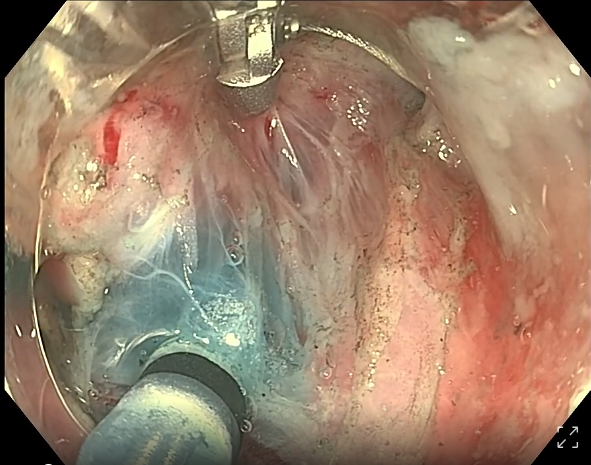

• endofaster内镜机器人辅助胃esd(粘膜下血管处理)

endofaster内镜机器人辅助胃esd(粘膜下血管处理)